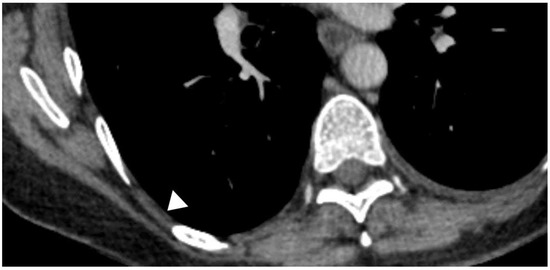

13. Ultrasound

14. CT